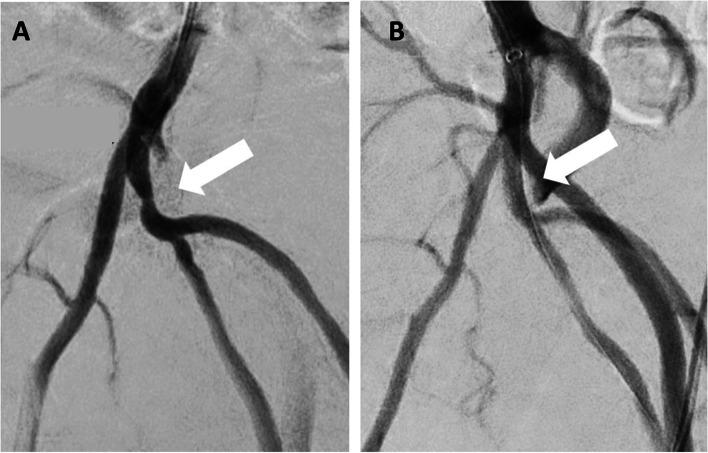

Angioplasty and stenting have emerged as endovascular treatment options for arteriogenic erectile dysfunction over the past few years. Considerable anatomical variation of the erection related pelvic arteries can be challenging during these procedures, leading to time-consuming repetitive super-selective angiograms for navigation.

TECHNIQUE

We report a novel technique of using C-arm Cone-Beam CT and vessel navigation software to facilitate super-selective catheterization.

在过去几年中,血管成形术和支架置入术已成为治疗动脉源性勃起功能障碍的血管内治疗选择。在这些手术过程中,与勃起相关的盆腔动脉存在相当大的解剖变异,这可能具有挑战性,导致需要耗时的重复超选择性血管造影来进行导航。

技术

我们报告了一种使用C形臂锥形束CT和血管导航软件来促进超选择性导管插入术的新技术。